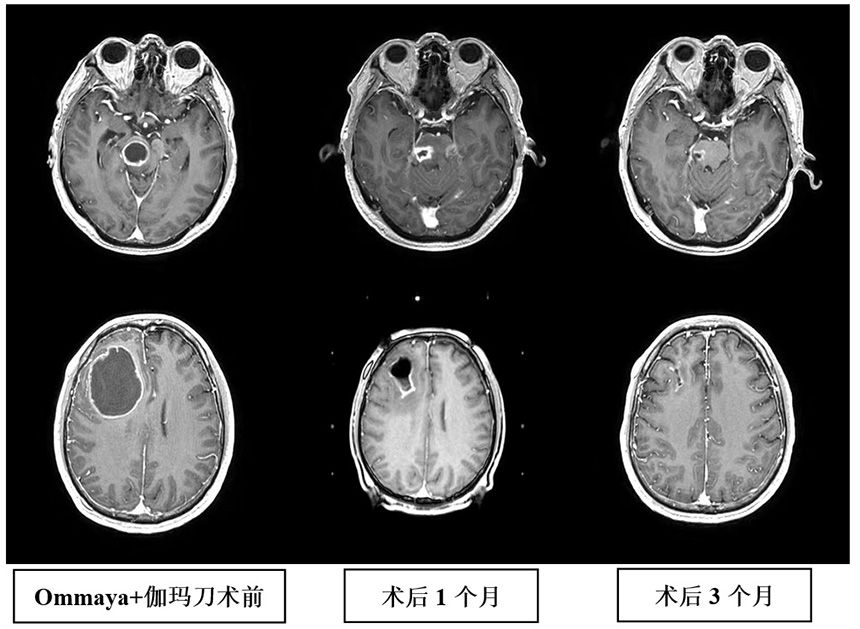

1、伽玛刀联合Ommaya囊穿刺引流术治疗巨大囊性脑转移瘤。穿刺引流可迅速改善占位效应,减少神经功能损害,结合伽玛刀治疗,提高病灶的局控率,当囊性病灶位于脑干等重要功能部位时,治疗效果更加明显。2018年12月,我们在上海脑转移瘤高峰论坛分享了此项经验。